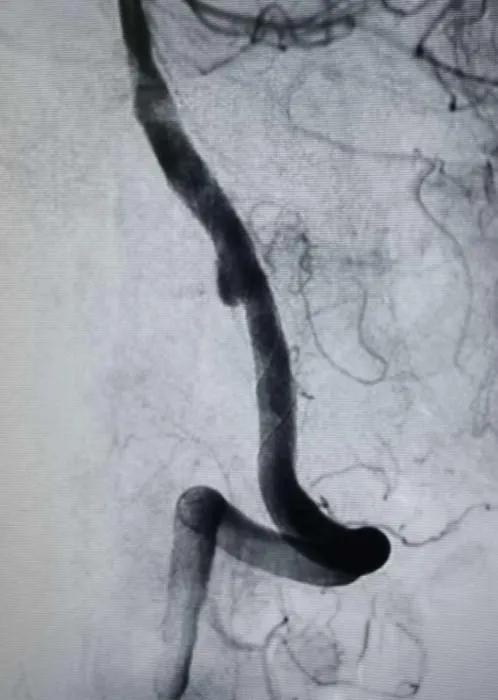

连接高压肝素盐水冲洗装置,6F导引导管在超滑导丝引导下超选进入左椎动脉入路段,行左椎动脉3D旋转造影并选取工作位,见左椎动脉V4段夹层动脉瘤,瘤颈约0.9cm,载瘤动脉约3.7mm(见下图)。

术中诊断:左侧椎动脉V4段夹层动脉瘤。